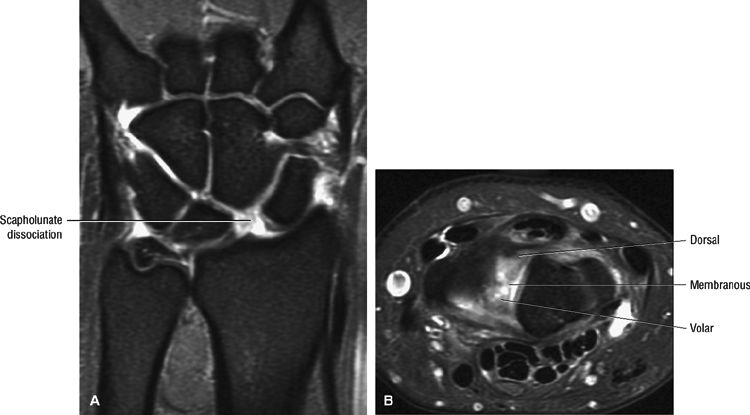

Dissociation (Fig. 10.96), indicated by an increased scapholunate gap (more than 3 mm), comparable to the Terry Thomas sign on radiography

DISI with dorsal tilting of lunate, an increased capito-lunate angle (more than 30°), and an increased scapho-lunate angle (more than 80°) (Fig. 10.98)

Complete ligamentous disruption with a fluid-filled gap and synovial fluid communication between the radiocarpal and midcarpal compartments

Disruption of the dorsal component of the scapholunate ligament